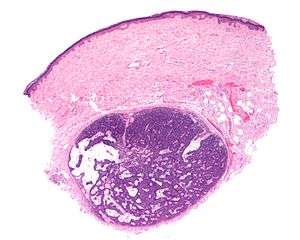

| Micrograph of a spiradenoma (bottom-center of image). H&E stain. | |

Spiradenoma, also spiroma [1][2] or eccrine spiradenoma,[3] is a cutaneous condition that is typically characterized, clinically, as a solitary, deep-seated dermal nodule of approximately one centimeter, occurring on the ventral surface of the body.[4]:666[5] Spiradenoma lesions are benign sudoriferous tumors,[6] and have also been described as cystic epitheliomas of the sweat glands.[7]